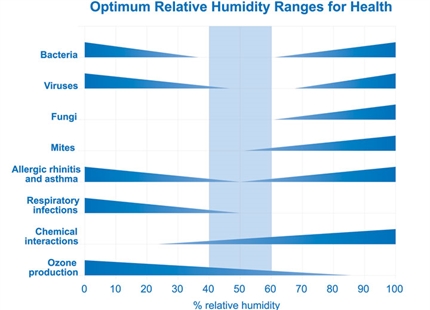

The study offers insight into why the flu is more prevalent when the air is dry. “It’s well known that where humidity drops, a spike in flu incidence and mortality occurs. If our findings in mice hold up in humans, our study provides a possible mechanism underlying this seasonal nature of flu disease,” said Iwasaki.

While the researchers emphasized that humidity is not the only factor in flu outbreaks, it is an important one that should be considered during the winter season. Increasing water vapor in the air with humidifiers at home, school, work, and even hospital environments is a potential strategy to reduce flu symptoms and speed recovery, they said.